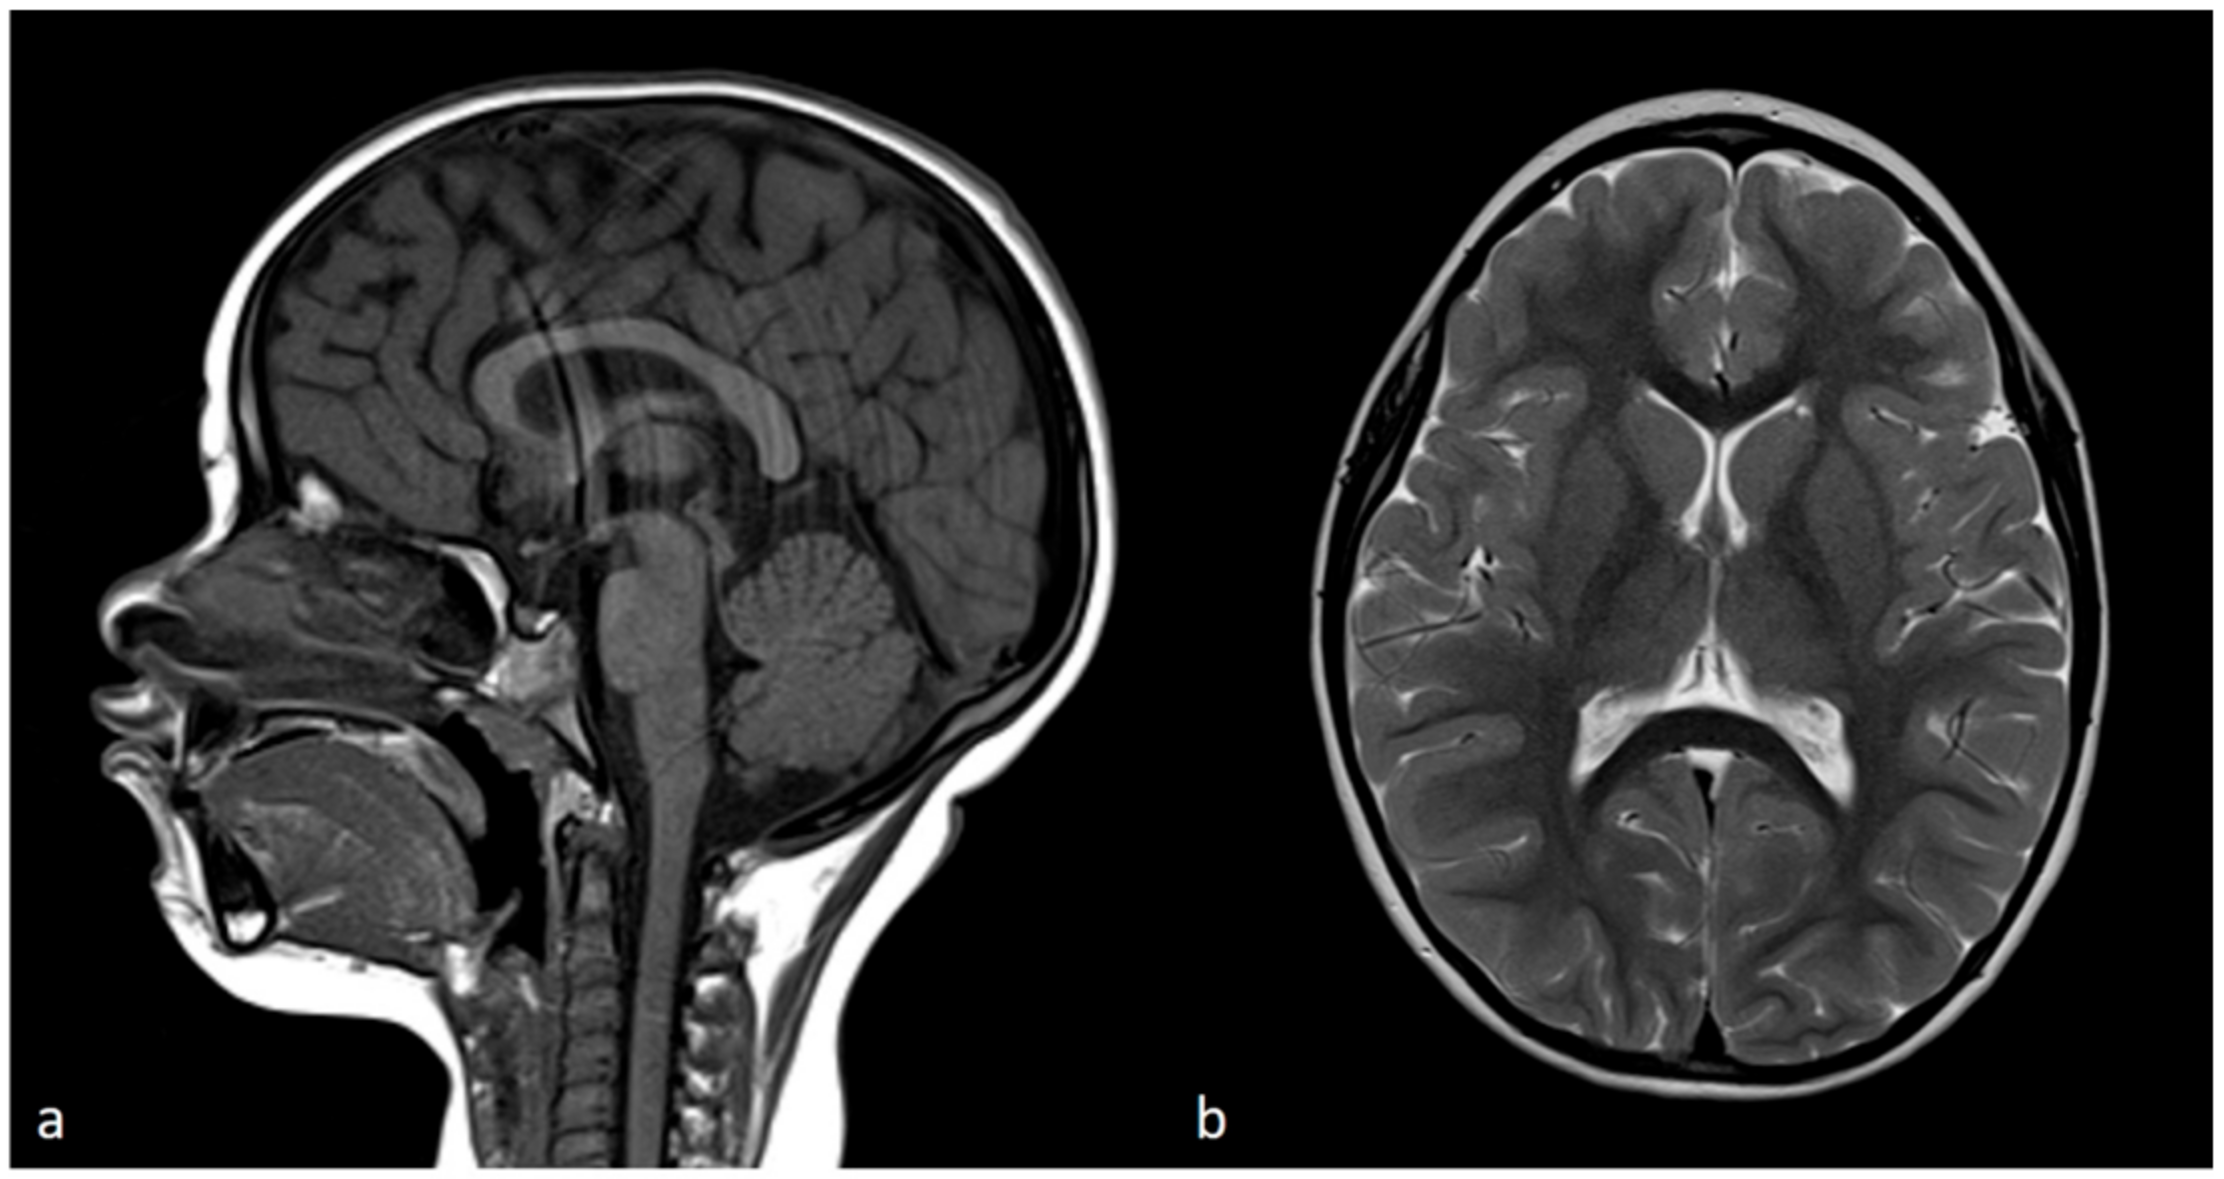

3.1. Clinical Findings